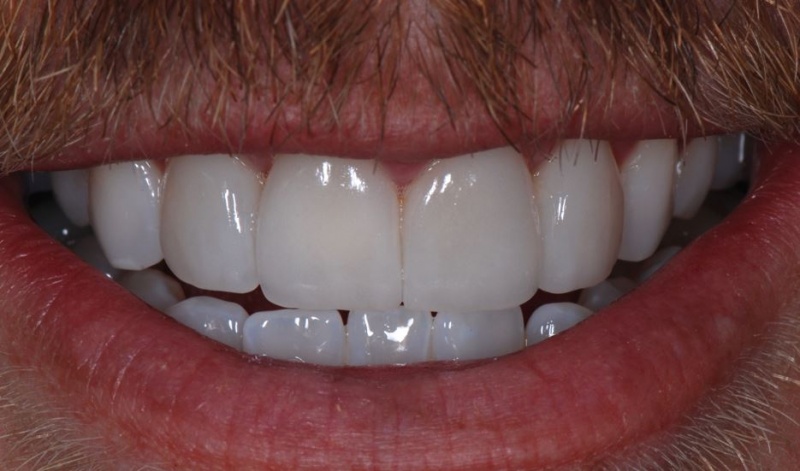

- Clinical: Finishing Veneers

- Longevity Expectations